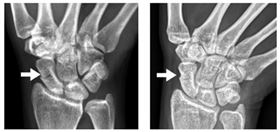

女騎車擦撞手腕撐地挫傷 竟釀舟狀骨骨折

35歲的彭小姐,因騎車上班途中不慎擦撞,造成手部撐地...